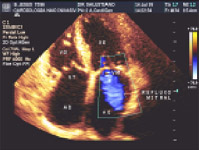

3.2 Ecocardiograma com Doppler Colorido

Esta modalidade de exame ecocardiográfico consagrou-se como fundamental no avanço da cardiologia e teve seu assentamento clínico no meados da década de 80. O ecocardiograma com Doppler em Cores, como é chamado, constitui o mais sensível recurso não invasivo (sem necessidade de contraste) para a observação do fluxo sangüíneo e sua dinâmica dentro das câmaras cardíacas e vasos. Este método atualmente é de eleição e indispensável para uma completa avaliação de patologias cardíacas que causam sopros e/ou shunts (valvulopatias, cardiopatias congênitas etc.).

O termo "em cores", que pode sugerir equivocadamente uma relação com efeitos "cosméticos" dispensáveis ao diagnóstico, remete, pelo contrário, as informações essenciais para se avaliar a severidade de cardiopatias que cursam com o distúrbio do fluxo sangüíneo. Assim, é importante que na solicitação desse recurso diagnóstico seja utilizado o termo em Cores, isto é, Ecocardiograma com Doppler em Cores.